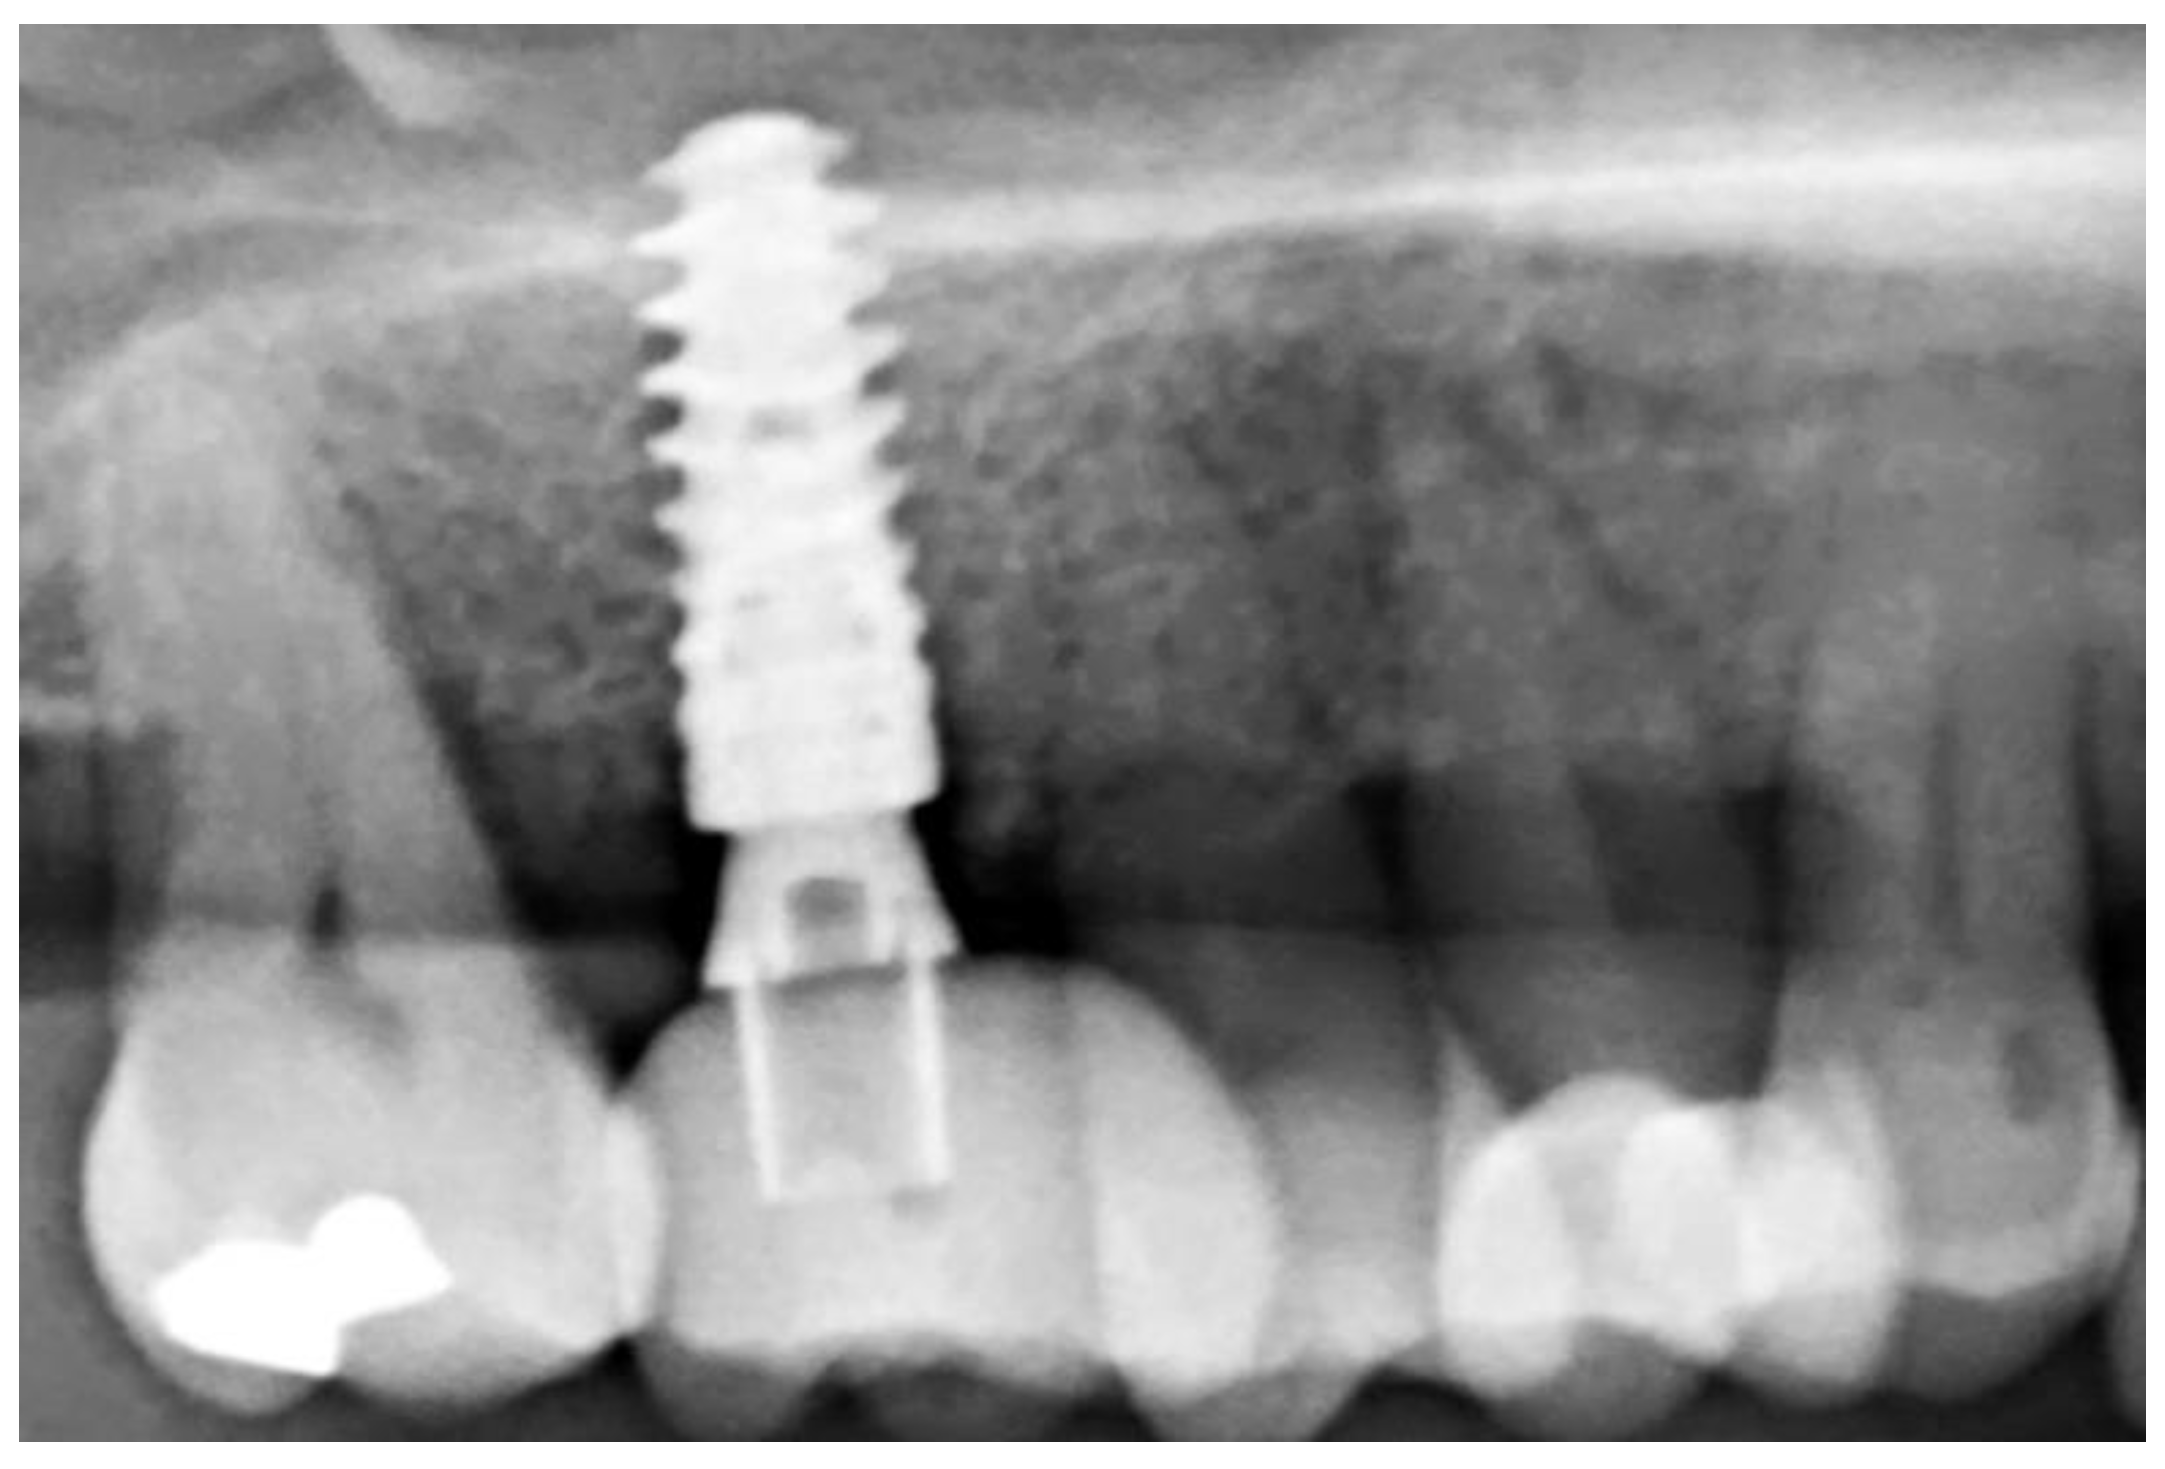

2. Materials and Methods

3.2. Ridge Dimension